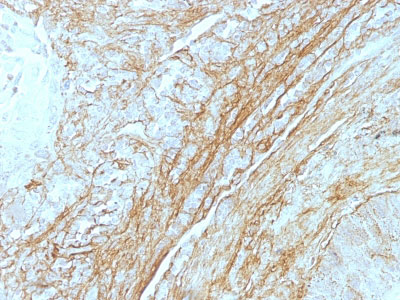

Tenascin C (Stromal Marker For Epithelial Malignancy) Antibody - With BSA and Azide

Mouse Monoclonal Antibody [Clone T2H5 ]

In Western blotting, it reacts with two bands of ~MW of 210kDa and 300kDa, identified as two isoforms of Tenascin C. Specificity of this MAb is validated by sequential immunoprecipitation with a PAb against Tenascin C. Tenascin C is a multifunctional, disulfide-linkedĀhexameric extracellular matrix glycoprotein expressed in association with mesenchymal epithelial interactions during development and in the neo-vasculature and stroma of undifferentiated tumors. In adults, it is restricted to certain epithelial-stromal interfaces and increases markedly in hyper-proliferative diseases and in stroma of many neoplasms, including gliomas, breast, squamous and lung carcinomas.